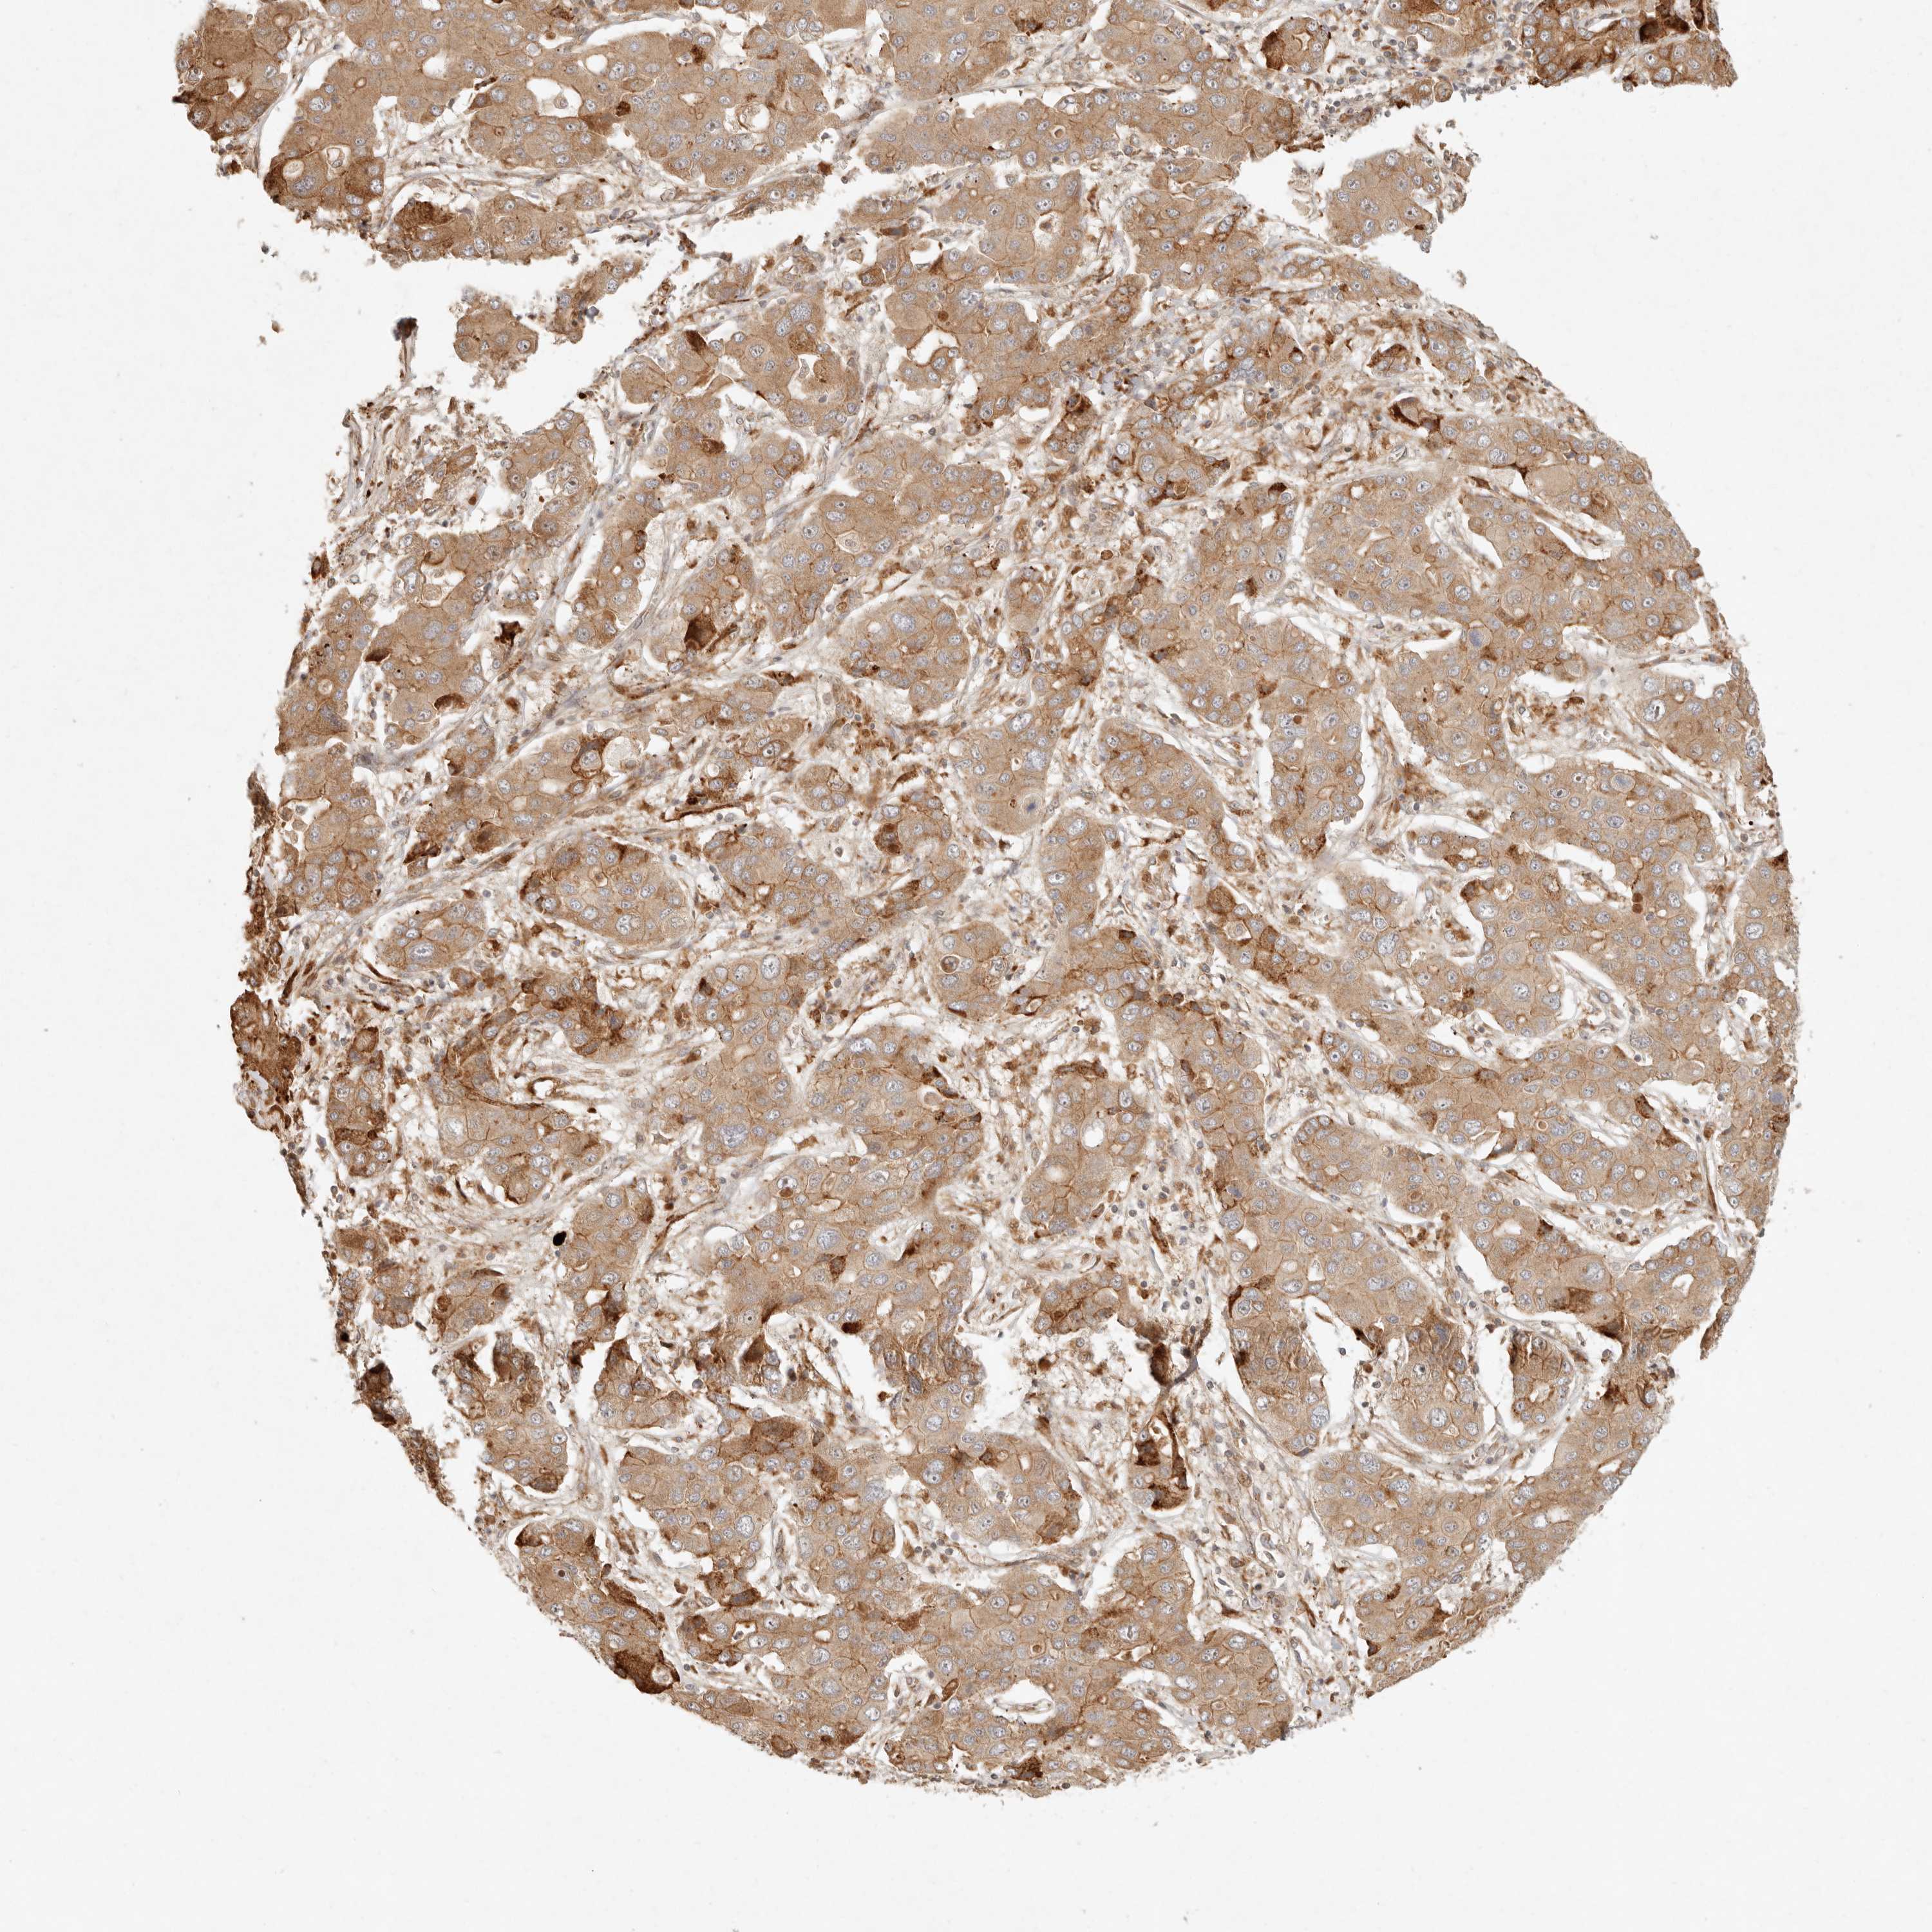

LIVER CANCER - Protein expressioni

A mouse-over function shows sample information and annotation data. Click on an image to view it in a full screen mode. Samples can be filtered based on level of antibody staining by selecting one or several of the following categories: high, medium, low and not detected. The assay and annotation is described here.

Note that samples used for immunohistochemistry by the Human Protein Atlas do not correspond to samples in the TCGA dataset.

Antibody stainingi

Antibody staining in the annotated cell types in the current human tissue is reported as not detected, low, medium, or high, based on conventional immunohistochemistry profiling in selected tissues. This score is based on the combination of the staining intensity and fraction of stained cells.

Each image is clickable and will lead to virtual microscopy that enables deeper exploration of all samples and also displays staining intensity scores, fraction scores and subcellular localization as well as patient and tissue information for each sample.

Antibody HPA024770

Antibody HPA027115

Staining

High

Medium

Low

Not detected

Intensity

Strong

Moderate

Weak

Negative

Quantity

>75%

75%-25%

<25%

None

Location

Nuclear

Cytoplasmic/membranous

Cytoplasmic/membranous,nuclear

Cholangiocarcinoma

Carcinoma, Hepatocellular, NOS